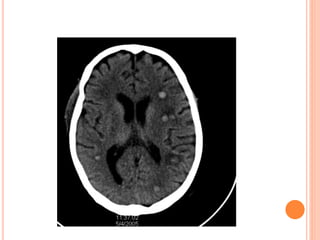

This document summarizes aspergillosis, including invasive pulmonary aspergillosis (IPA), chronic necrotizing aspergillosis (CNA), and aspergilloma. Aspergillus is a common mold that can cause a variety of pulmonary diseases. IPA predominantly affects immunocompromised patients and presents as pneumonia. Diagnosis involves tissue biopsy, galactomannan testing, and imaging. Voriconazole is recommended treatment. CNA occurs in patients with underlying lung disease and is characterized by slow lung tissue invasion. Itraconazole is effective treatment. Aspergilloma involves a fungus ball in a pre-existing lung cavity.